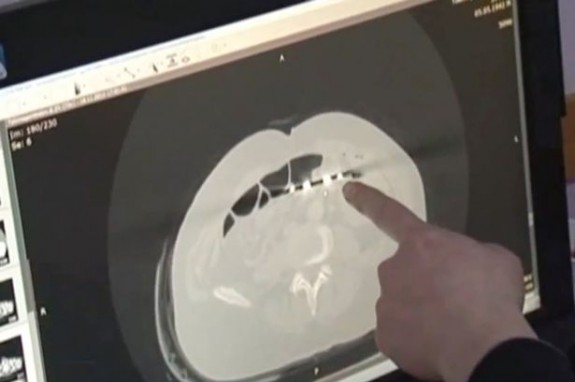

Doktor Baurzhan Aybaev ostao je šokiran kad je vidio rendgenski snimak.

”Nikad nisam vidio ovakvo nešto. Nekad se desi da ostane neki mali dio hirurške opreme, ali da to budu makaze, to je nevjerovatan propust” – rekao je doktor, te dodao:

”Hirurgu koji mu je radio operaciju su očito promakle. Sada mu treba nova operacije da uklonimo makaze.”